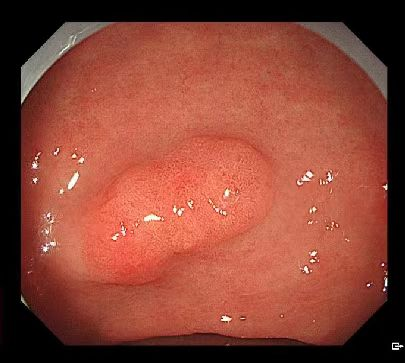

胃癌早起